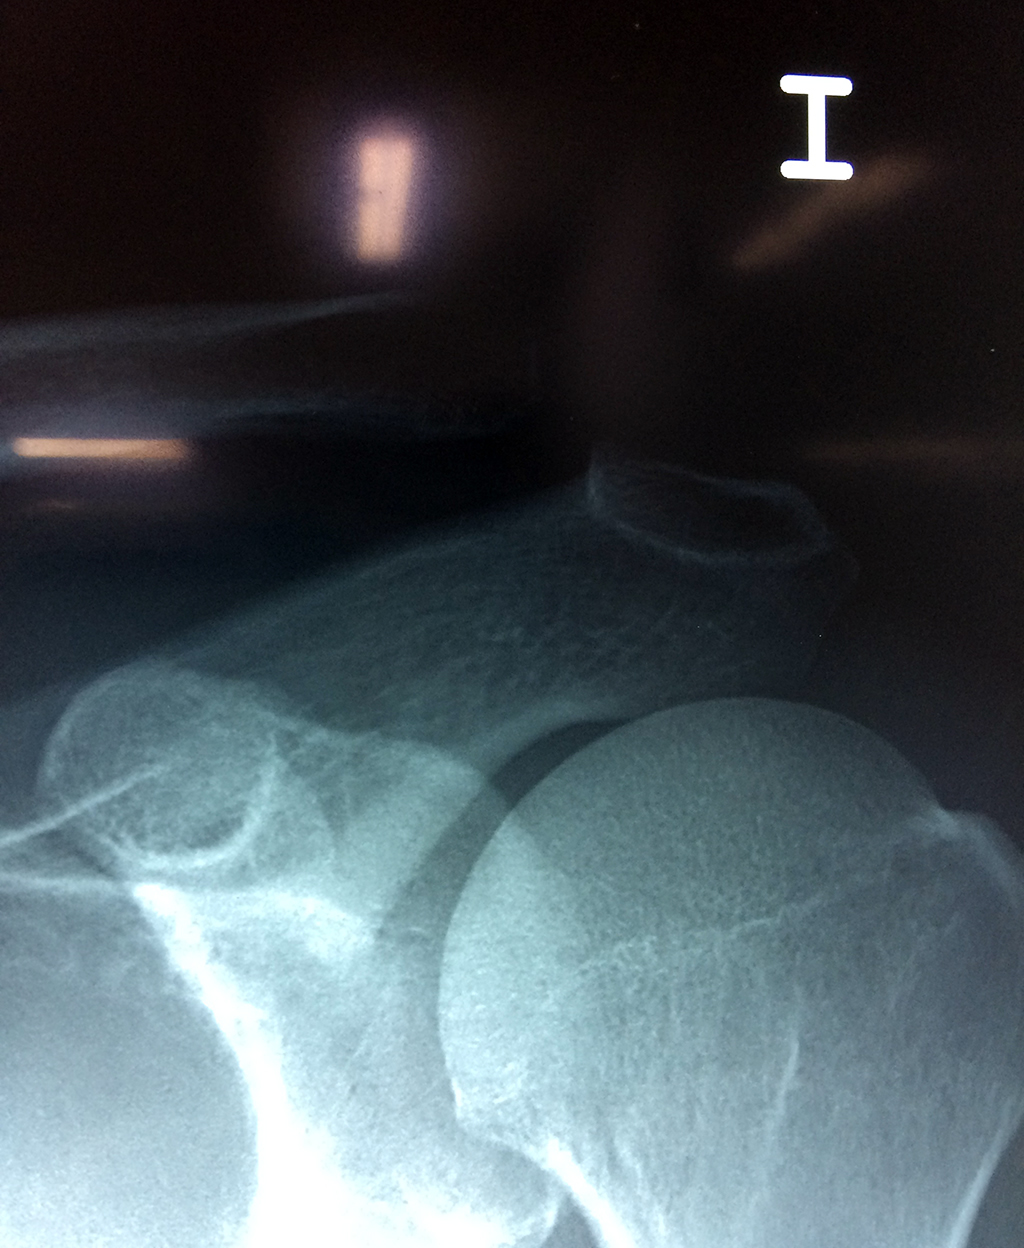

Cirugía de Fémur - Clavícula

La clavícula es un hueso largo, con forma de "S" itálica, situado en la parte anterosuperior del tórax. Junto con la escápula forman la cintura escapular. Se puede palpar por toda su longitud y se extiende del esternón al acromion de la escápula, siguiendo una dirección oblicua lateral y posterior.